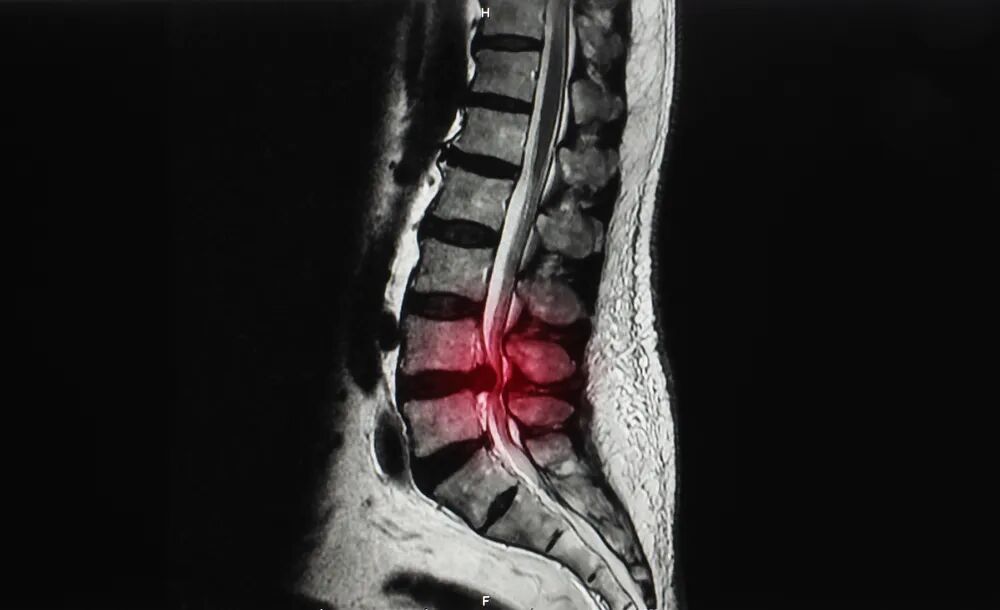

如果說脊柱是人體的支柱,腰椎就是脊柱的根基。腰椎間盤,作為腰椎中間的一個“軟墊子”,對腰椎起著支撐、連接和緩沖震蕩的作用。

腰椎間盤突出癥是因腰椎間盤變性、纖維環(huán)破裂,髓核組織突出壓迫和刺激神經(jīng)根、馬尾神經(jīng)所引起的一種綜合征,是導致腰腿痛最常見的原因之一。

腰椎間盤突出癥常發(fā)生于青、中 年。腰椎間盤突出癥發(fā)病的基礎是椎間盤的退行性變,腰部外傷或工作、生活中反復的輕微損傷導致髓核突出產(chǎn)生癥狀。